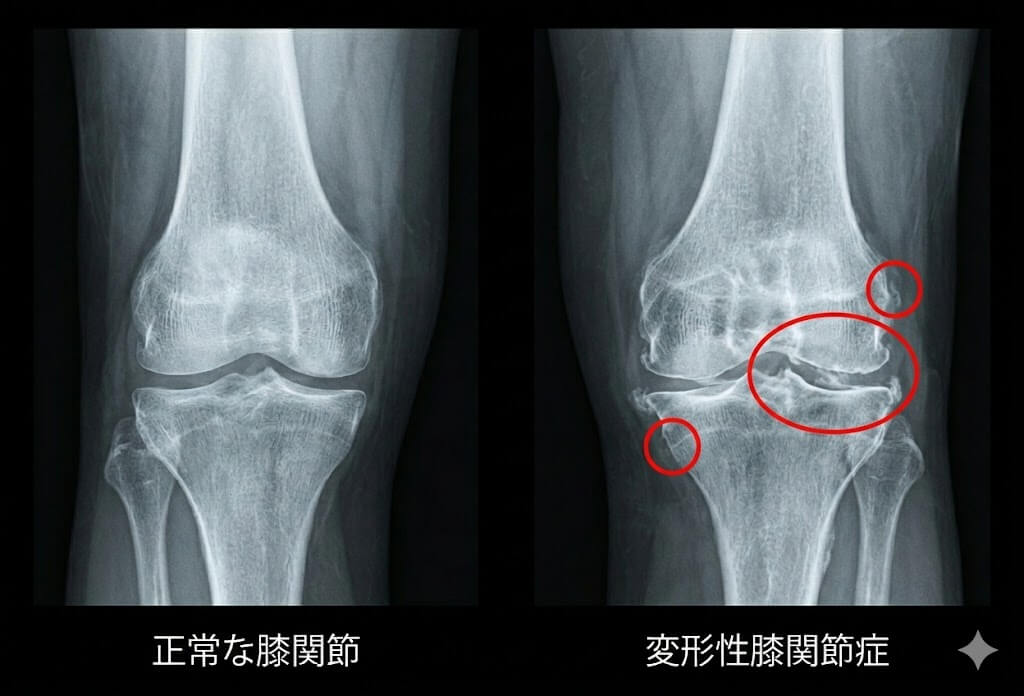

診断名(変形性膝関節症など)をもらったら、そこからは「動きのプロ」である私たち整体の出番です。

レントゲンやMRIを使って、骨や軟骨が物理的にどう壊れているかを正確に把握することは初期対応として非常に重要です。

レントゲンには「骨」は写りますが、痛みの本当の原因になりやすい「筋肉の硬直」「関節のねじれ」「歩き方の癖」は写りません。